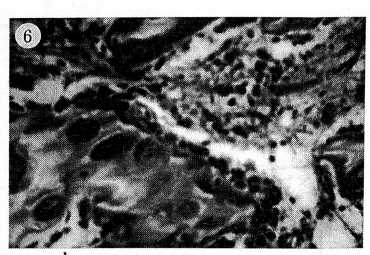

Операция типа Э.И. Шаиро сопровождалась полнокровием сосудов, хорошо заметным в течение первых 2 мес после вмешательства. Однако к исходу 2-го месяца оно уменьшалось. Выраженное полнокровие сосудов костных балок и костного мозга отмечалось и после межвертельной остеотомии. Эта гиперемия сохранялась до конца периода наблюдения, т.е. в течение 3 мес (рис. 5). Обращала на себя внимание более высокая степень васкуляризации костного мозга после данной операции. Очаги альтеративных изменений костного мозга после межвертельной остеотомии отличались меньшими размерами и выявлялись реже, чем после костной аутопластики. Репаративные процессы, представленные остеобластической и остеопластической реакциями, также имели различную степень выраженности — более оживленными они были после межвертельной остеотомии (рис. 6). Данные обстоятельства можно поставить в связь с более обильной васкуляризацией и полнокровием головки бедренной кости, а также с отсутствием дополнительной травматизации, вызываемой костной аутопластикой. Консолидация в зоне остеотомии в 80% случаев наступала через 8 нед и в 100% — к концу 3-го месяца наблюдения.

Таким образом, результаты гистологического исследования свидетельствуют, что межвертельная остеотомия сопровождается более выраженными и стойкими признаками как повышенного кровоснабжения головки бедренной кости, так и активности репаративных процессов.

Рис. 6. Микрофотограмма препарата через 8 нед после межвертельной остеотомии: оживленная остеобластическая и остеопластическая реакция.